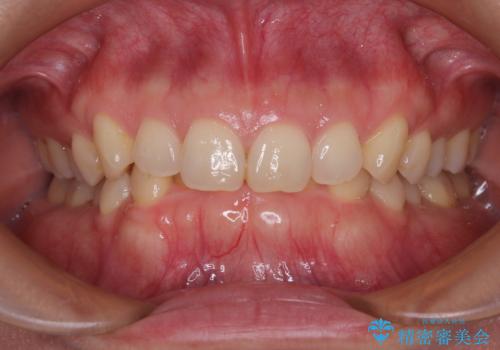

隠れた前歯が気になる ディープバイトのワイヤー矯正治療

- 下顎前歯が完全に隠れてしまっていることを気にして来院された患者様です。

下顎の臼歯が手前に傾斜していることで咬み合わせが深くなってしまい、下顎前歯が見えないほどに上顎前歯が覆い被さっている状態でした。